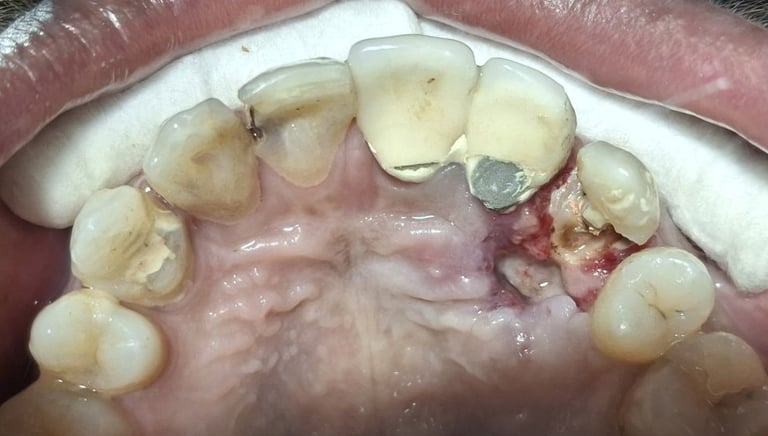

Before

All images shown here are real teeth cleaning cases treated at our clinic with patient consent.

Professional teeth cleaning helps remove plaque, tarter, and surface stains that regular at home brushing can not.

At Shree Dental Care, teeth cleaning is performed gently with focus on patient experience, comfort and long term oral health.